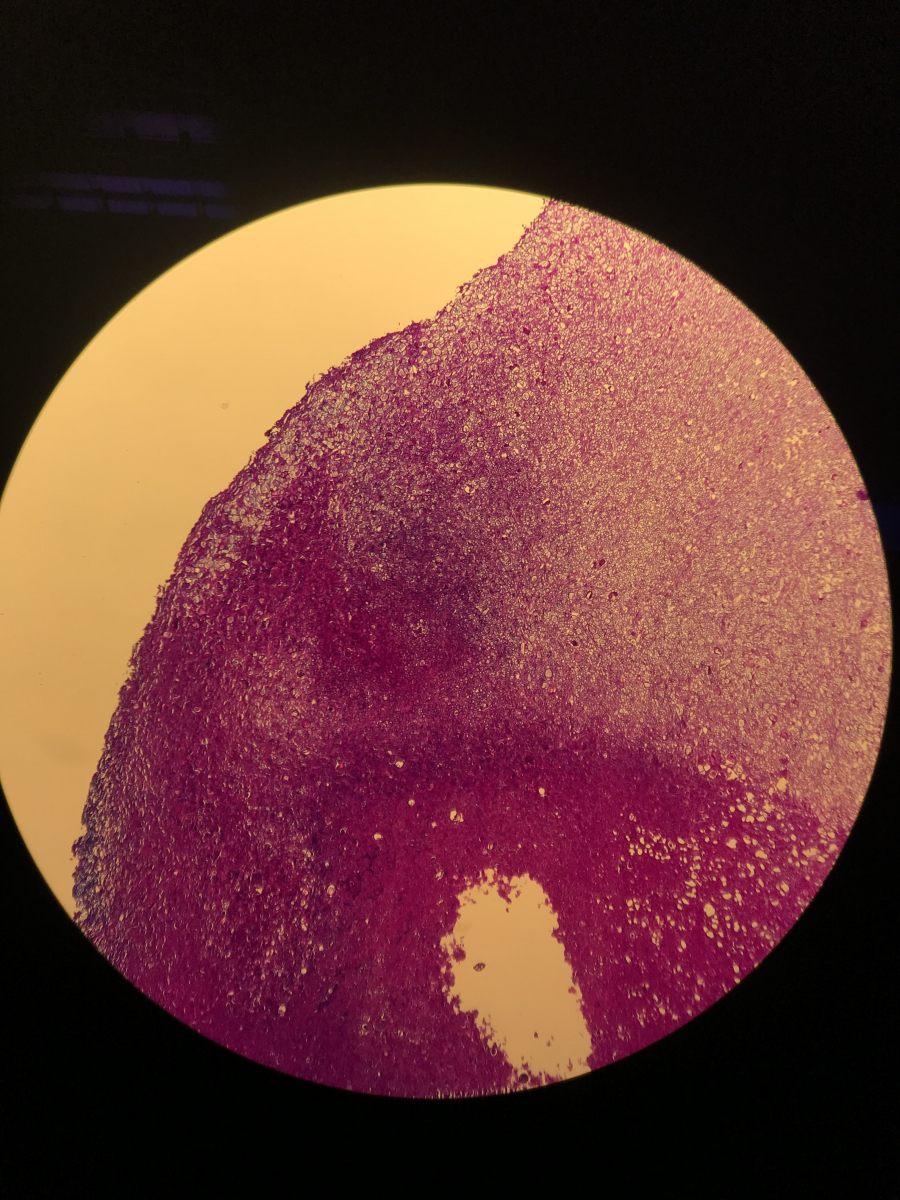

Das Material liegt mich seit knapp 2h vor und ich komme damit einfach nicht wirklich voran. Denn nicht nur das mir die passende Literatur dafür fehlt, viel schlimmer noch… Ich finde in keinem einzigen Präparat auch nur eine Spur von Sporen.

Morgen früh werde ich eine dünne Scheibe bei uns im Labor histologisch aufarbeiten… damit wir eine lichtdurchlässige Gesamtsicht erhalten ca. 1-3µm dick.